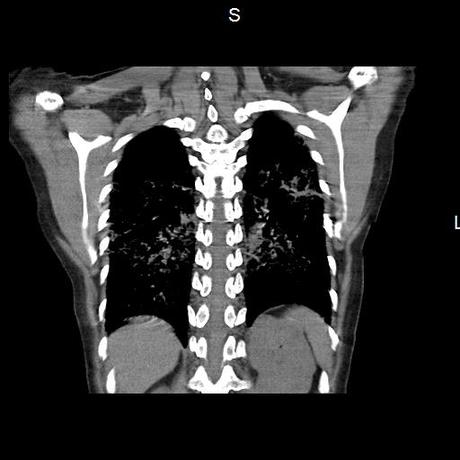

Se realiza volumen de tórax en fase simple, desde los opérculos torácicos hasta los hemidiafragmas, observándose:

El parénquima pulmonar con areas parcheadas difusas en vidrio despulido combinadas con otras areas hipodensas de baja atenuación debidas a atrapamiento aéreo y engrosamiento intersticial y zonas de fibrosis de predominio en lóbulos medios e inferiores de ambos pulmones.

- LOS HALLAZGOS PUEDEN ESTAR EN RELACIÓN A NEUMOPATIA INTERSTICIAL PROBABLE ETIOLOGIA HIPERSENSITIVA VS AUTOINMUNE/BACTERIANA/FUNGICA.